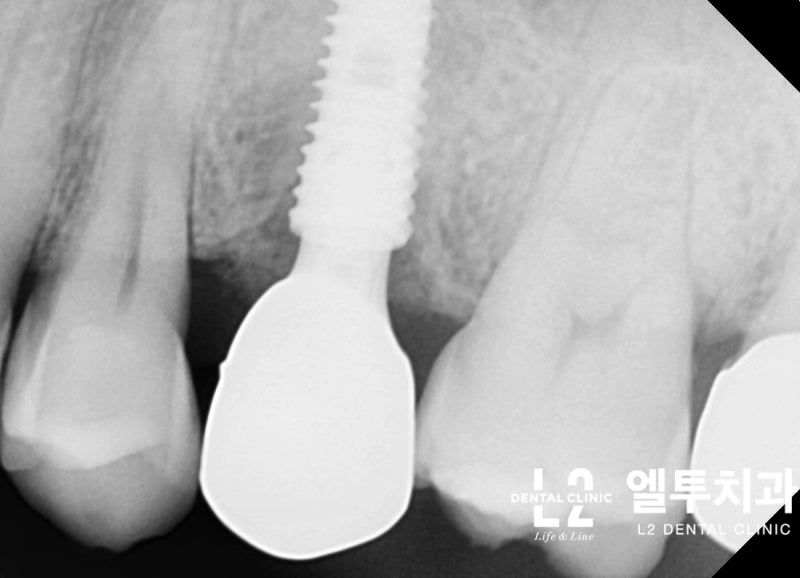

큰어금니와 작은어금니의 갈라진 치아 모습에는 차이가 있는데, 큰어금니의 갈라진 치아는 대부분 “기능적 팁” 쪽, 즉 치아에서 더 큰 스트레스를 받는 부분에서 발생합니다. (아래 포스팅 참조) https://blog.naver.com/sunnyflow/222654941394 Q-ray 촬영으로 어금니 크랙(균열)을 미리 확인하고 대비할 수 있습니다. 닥터&치주과의사 최순호 입니다 오늘은 어금니 중문으로 가는데… blog.naver.com 물론 기능교두의 기능교두는 작은 어금니에도 크랙이 생기는 경우가 많은데, 치아가 부러지는 원인. 음식을 씹을 때 위아래로 씹지 말고 나란히 씹는다. 이것을 치과 용어로 “Lateral Guidance”라고 하는데 위 사진에서 색종이(교합용지)를 찍으면 치아에 가해지는 힘이 화살표 방향으로 퍼지는 것을 볼 수 있습니다. 다시 케이스로 돌아가서 왼쪽 위 어금니가 이전에 근관치료와 크라운 치료를 받았고 씹을 때 불편하다고 하셨습니다. X-레이를 보면 치근/크라운 치료를 받은 어금니 주변에 어두운 그림자가 보일 것입니다. 뼈가 녹으면서 “J자 모양”이 되고 X-레이에서 보이는 이러한 방사선학적 변화는 종종 치아의 깊은 층에 균열이 있음을 나타냅니다(크라운 뿌리 균열, 뿌리 균열 = 치근. 갈라진 치아). 측방 구강 내부에서 송곳니가 곧게 연마되는 것과 같이 측면 안내 중에 치아가 강한 측면 힘을 받는 것으로 추론할 수 있습니다. 이 힘이 계속되면서 작은 어금니 부위에도 깊은 균열이 발생했다. 이 정도까지 치아 사이의 간격이 벌어지면 치과에서 치료할 방법이 없기 때문에 발치 후 임플란트 치료를 권해드립니다. 발치 모습. 화살표가 가리키는 부분을 자세히 보면 치아의 머리 부분에서 시작하여 치근 깊숙이 뻗어나가는 크랙(균열)을 볼 수 있습니다. 입 안의 세균이 미세하게 새는 것은 균열선을 따라서만 진행될 수 있어 잇몸뼈가 재흡수되어 씹을 때 통증이 발생합니다. 임플란트 수술은 발치 당일에 시행하고 일정 기간 치유 후 작은 어금니 부위에 임플란트 크라운을 식립합니다. 이러한 현상을 가진 환자들은 이상한 점을 발견할 수 있는데, 반대측 치아에서도 비슷한 상황을 관찰하는 경우가 매우 흔하다. 반대쪽 소구치를 보면 잇몸뼈가 주변 치아와는 매우 다른 방식으로 흡수되는 것을 볼 수 있습니다. 이 치아 역시 치근 치료와 크라운 치료를 한 치아이기 때문에 치아의 치근쪽에 크랙이 나타난 것으로 의심됩니다. 문제 치아 옆의 작은 어금니도 균열이 의심되는 Q-선 형광 검사에서 관찰되었습니다. 금이 간 치아가 강하게 의심되었지만 어쨌든 심각한 치은 골 흡수가 관찰되었으므로 “진단”+ “치료”의 목적으로 치은 박리를 시행했습니다. (환자분들이 아프지 않을때까지 보관하라고 하셔서 알고 있습니다.) 이렇게 입에 금이 간 치아가 많은 분들은 예방적 크라운 치료를 권해드리고 있습니다. 크라운 치료는 앞니의 단점이 있지만 “치아 보호”가 최우선입니다. 위에서 언급한 2개의 치아 외에도 양쪽 소구치에 크랙이 관찰되어 더 진행하면 바로 발치할 수 있어 환자에게 크라운 치료를 알리고 진행하였다. 너무 늦기 전에… 깨진 치아를 무시하면 종종 손을 사용하지 않고 발치 및 임플란트 치료가 발생할 수 있습니다. https://blog.naver.com/sunnyflow/222413456775 치아가 깨지거나 부러져 부주의로 발치를 하게 된 사례 안녕하세요. L2치과의원장 최순하오 원장입니다. 최근 치과에 다녀온 환자에서… blog.naver.com 바로 씹어도 통증이 없어도… 상당한 크랙이 관찰된다면 예방적 크라운 치료를 고려해보시는 것을 강력히 추천드립니다:) 오늘의 기사가 도착합니다. 끝. 스마트폰에서 위 부분을 터치하시면 다이얼로 전환됩니다.서울시 강남구 봉은사로 469, S-TOWER L2, 4층 치과